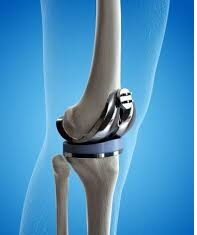

97 Year Old Indian Undergoes Knee Replacement Surgery at Fortis Hospital Vasant Kunj

Complex Total Knee Replacement Surgery was performed on 97-year-old woman suffering from severe Osteoarthritis

Delhi's Doctors at Fortis Hospital Vasant Kunj have successfully performed a total knee replacement surgery on a 97-year-old woman,...